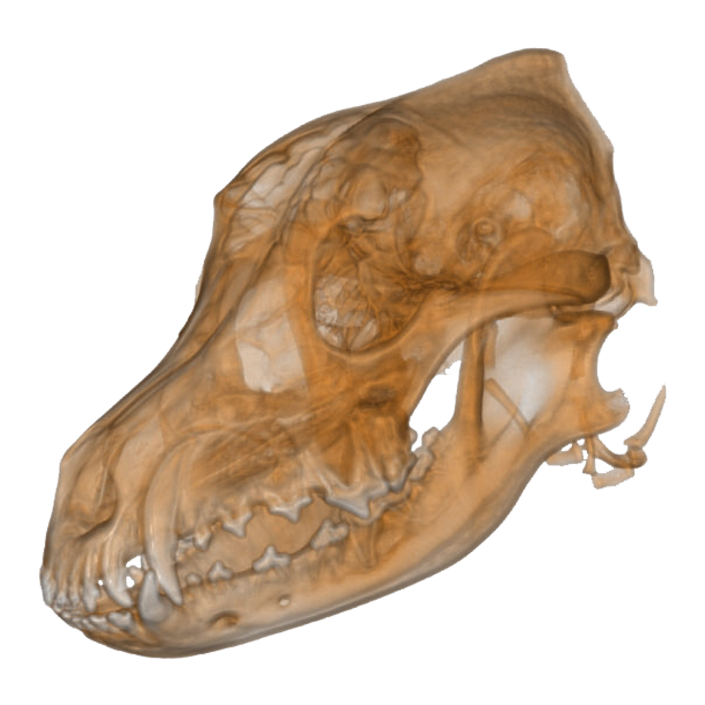

Das NewTom 5G XL VET Compact ist die ideale Lösung für Praxen mit geringem Platzangebot.

Dieses CBCT vereint die Vorzüge des NewTom 5G XL mit einem speziell entwickelten Carbon CBCT Tisch.